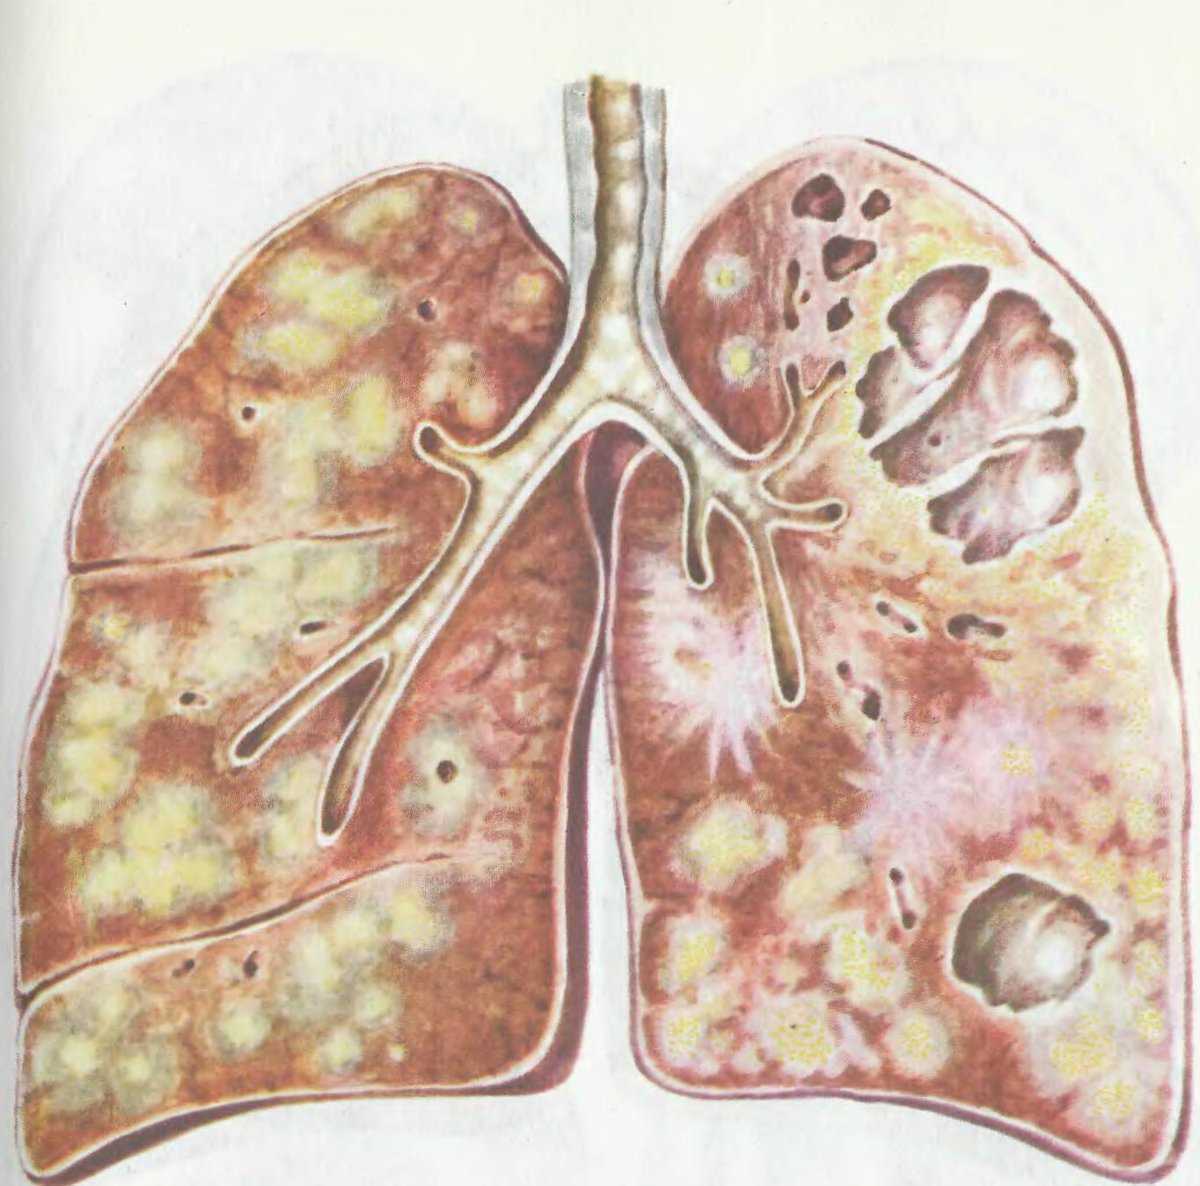

Симптомы и признаки туберкулеза: как распознать заболевание

Раздел: Визуальные уроки